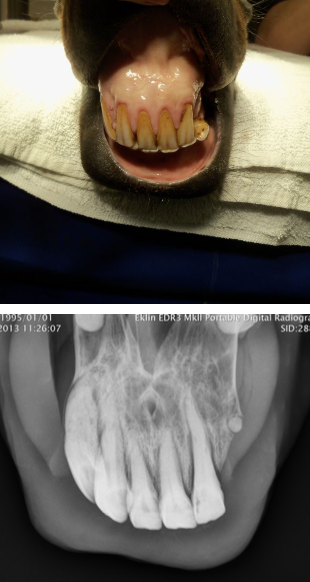

what is EOTRH?

progressive dental condition involving the incisors, canines, and premolars of aged horses internal and external resorption of dental structures and production of irregular cementum

what lesions/changes are seen with EOTRH?

gingival recession, calculus deposition, and firm bulbous enlargement of incisive bone over incisive reserve crowns

what is the treatment for EOTRH?

extraction of incisors